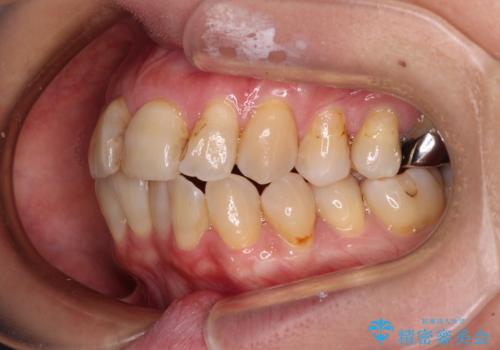

- 口元の突出感を気にして来院された患者様です。

上下前歯が著しく前突している状態であったので、上下左右の小臼歯4本を抜歯し、ワイヤー装置にて矯正治療を行うこととしました。

上顎左側は第二小臼歯に大きなむし歯があったため、通常は第一小臼歯を抜歯するところ、イレギュラーに第二小臼歯を抜歯することとしました。

抜歯する第二小臼歯の後方の歯は神経近くにまで及ぶむし歯があったため、事前に処置をしておき、矯正治療後にオールセラミッククラウンにて補綴治療を行うこととしました。